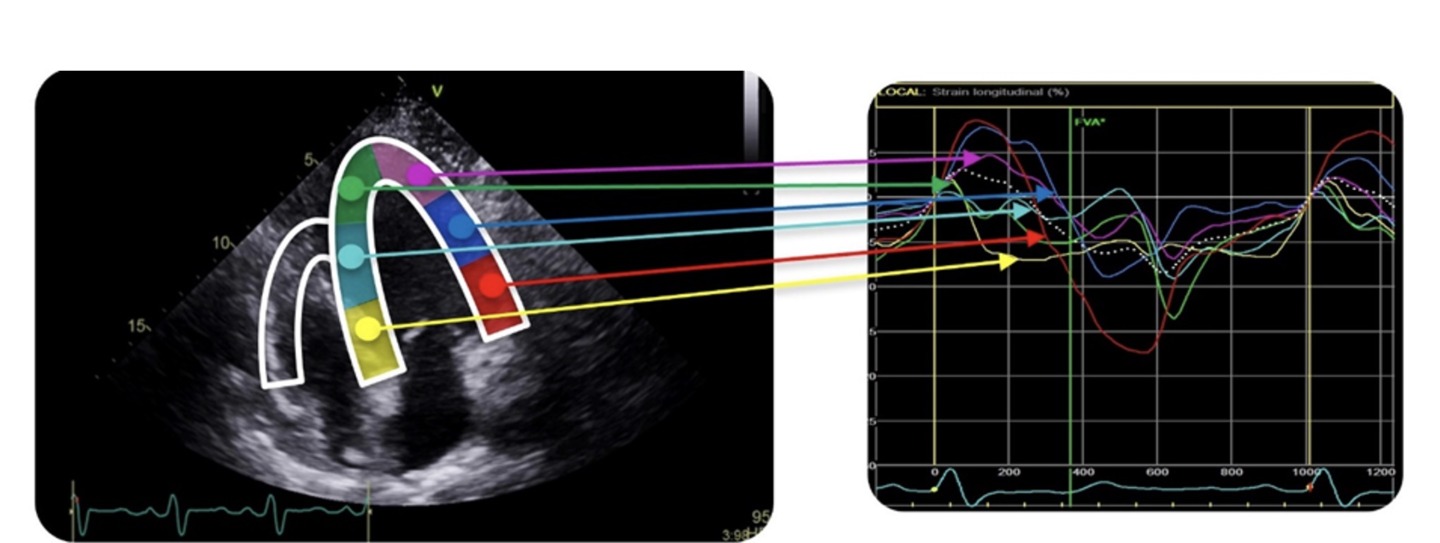

Déformations des segments (en couleur, à gauche) du ventricule gauche observés par échographie permettant d’analyser les mouvements de la paroi (à droite). Copyright LTSI.

Marion Taconné vient de Guérande, ce magnifique pays de mer, de sel et de marais. Cela ne l’a pas empêchée au fil de ses études de voyager puisqu’elle a choisi d’entrer dans le programme Erasmus qui l’aura emmenée en Suède. Ses travaux de thèse (elle entre dans sa dernière année) portent sur l’insuffisance cardiaque et sont dirigés par Mme Virginie Le Rolle, maître de conférences (MCU), et M Erwan Donal, professeur et praticien hospitalier (PUPH) au CHU Pontchaillou à Rennes.